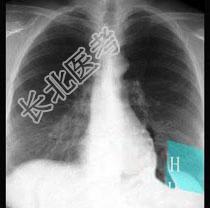

- 单项选择题在图所示正常胸部X线影像图像上,该英文字母所代表的肺段为 ( )

A、H代表内基底段

B、H代表前基底段

C、H代表外基底段

D、H代表后基底段

E、H代表背段